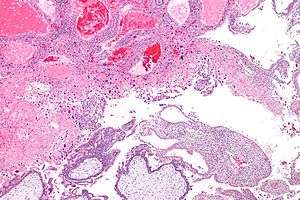

| Micrograph of intermediate trophoblast and a hydatidiform mole (bottom of image). H&E stain. | |